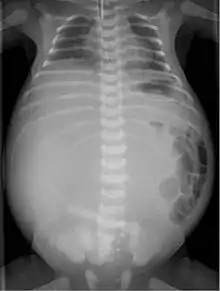

في 20% من الأطفال الذين يولدون بالتهاب الصفاق بالعقي؛ يحدث القيء وتظهر الأمعاء متسعة على الأشعة السينية وهو ما يتطلب عملية جراحية.

في بعض الأحيان، يتم تشخيص التهاب الصفاق بالعقي بناءً على الموجات فوق الصوتية [9] قبل الولادة حيث يبدو كما تكلسات داخل الصفاق.[10]